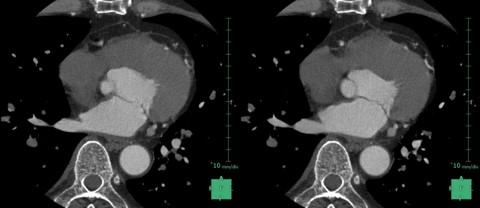

② SSF2.0によるアーチファクト低減と画像処理の容易化

SSF2.0はGE HealthCare社の最新の心臓CT画像動態補正技術である。前述した通り心臓全体の動き補正が可能な技術で、画像の動きをトラッキングし、モーションアーチファクトが抑制された静止画像を構築する。これにより、高心拍や不整脈の患者でも、高品質な心臓CT画像が得られる。SSF2.0は、冠動脈や大動脈弁、僧帽弁などの心構造疾患の診断や治療において、有用な情報を提供することができる。

当院では、SSF2.0を導入したことで補正後の画像では冠動脈を含むブレが低減され、VR等の画像処理が容易となり画像処理にかける時間を大幅に短縮することができた(Fig5,6)。

RevolutionCT_koyamakinen05.jpg

Fig5. SSF2.0 On/Offの比較